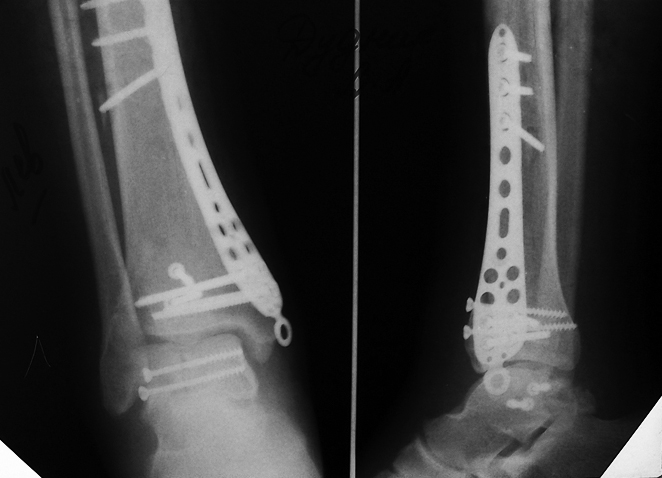

[Ortho] перелом таранной кости и пилона

Всем большое спасибо за участие и советы! На операции удалось

репонировать и зажать между основными отломками передние фрагменты

суставной поверхности, а вот задняя часть суставной поверхности-"мелкое

крошево", причём наружного кортикала там тоже нет. Фрагменты подняты,

под них подведён трансплантат, как ещё зафиксировать не придумал.